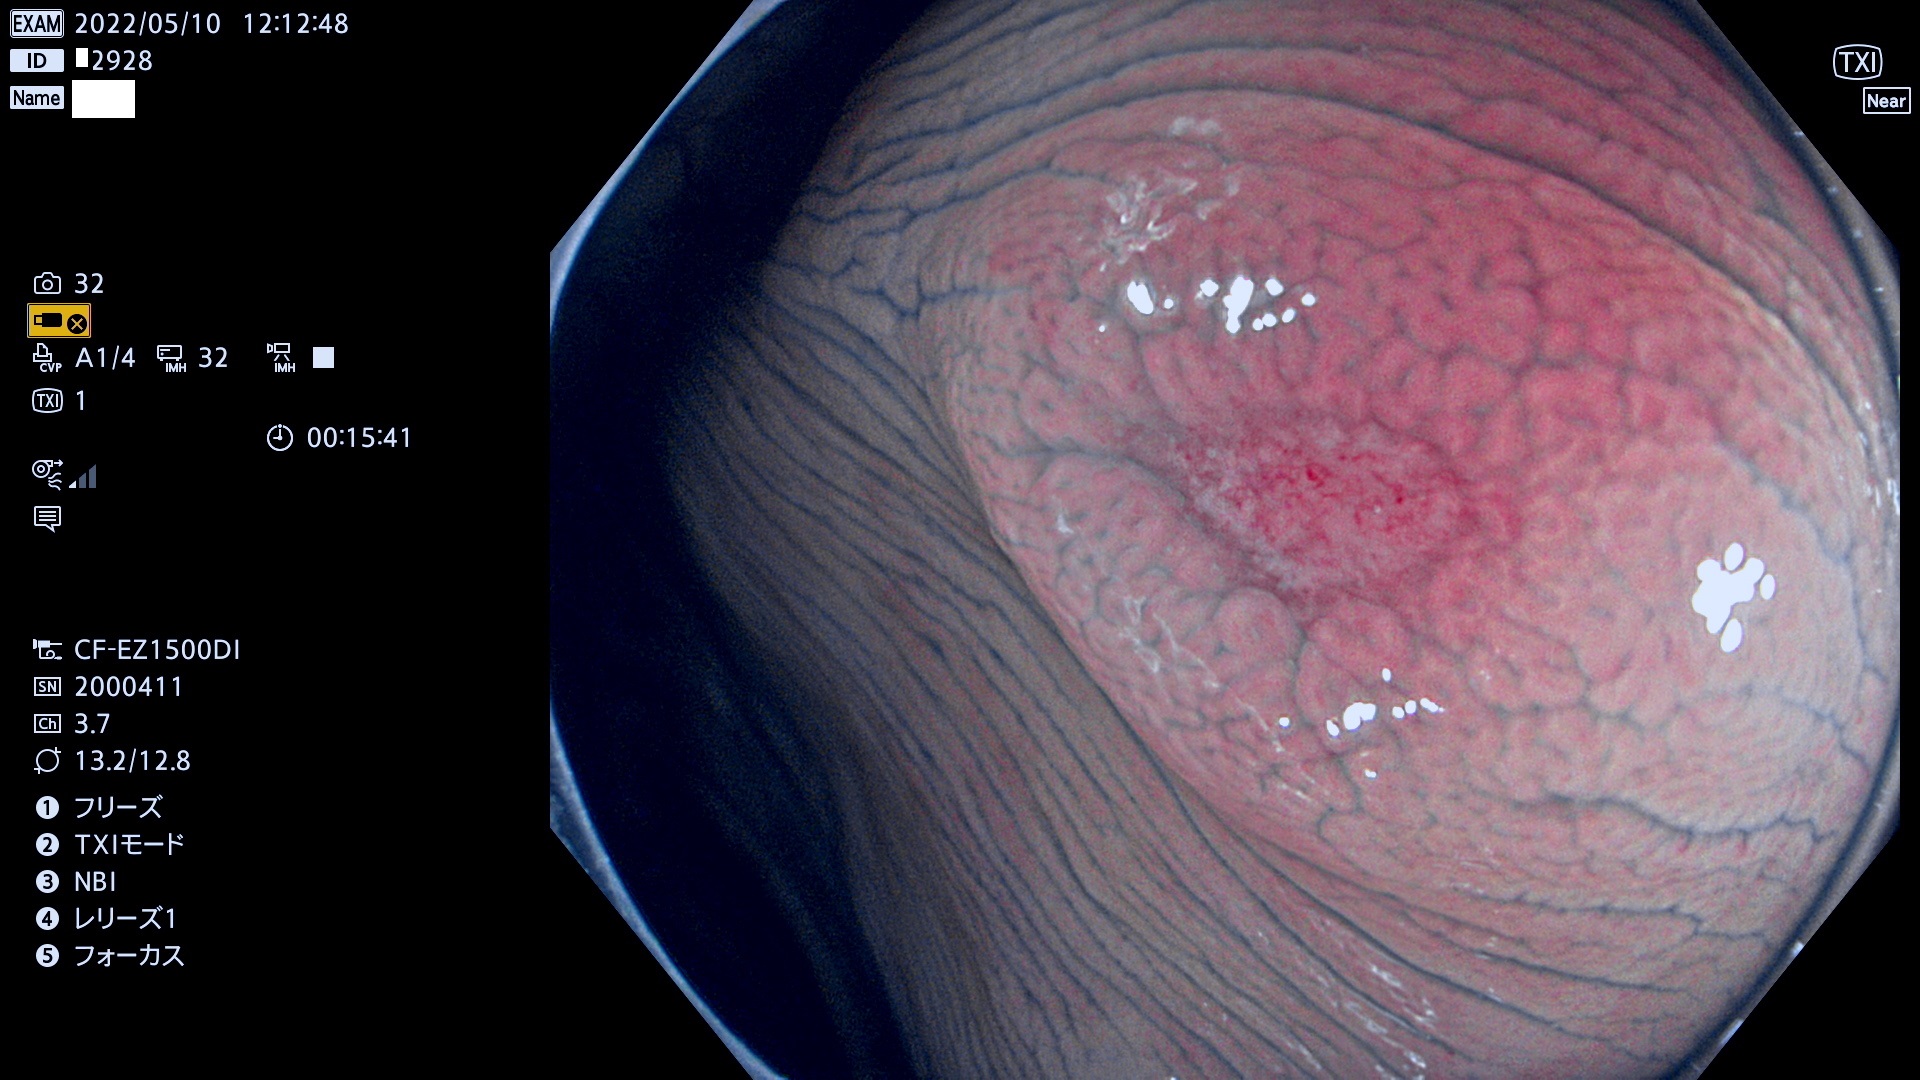

ビランと紛らわしいUc型腺腫(最も危険な前癌病変)

以下の写真は2019年に秋田日赤から報告された典型的な「ビランと紛らわしいUc型腺腫」です。この報告は大きな話題となりました。

このようなタイプの病態は解明されていませんが、私見としてはGALT型腺腫(粘膜下腺腫)ではないかと考えています。或いはSuperficially serrated adenoma =SuSAの類縁なのかもしれません。いずれにせよ、表面の観察(Pit診断)が無力な病態です。

以下は当院で経験した「ビランと鑑別の難しいUc型腺腫」です(全て、病理で腺腫を確認済み)。

このような病変は表面を拡大観察しても診断は不可能であり、現在の内視鏡診断の「限界を超えた病変」と言えます。現実的な対策は「典型的なビランと異なる」と感じたら、「コールド法で積極的に切除する」ことと考えます。もちろん「結局はビランだった(不要な過剰切除だった)」ということもあります。しかしコールド法なら重篤な合併症は稀であり、医師は切除を躊躇すべきではないと考えます。